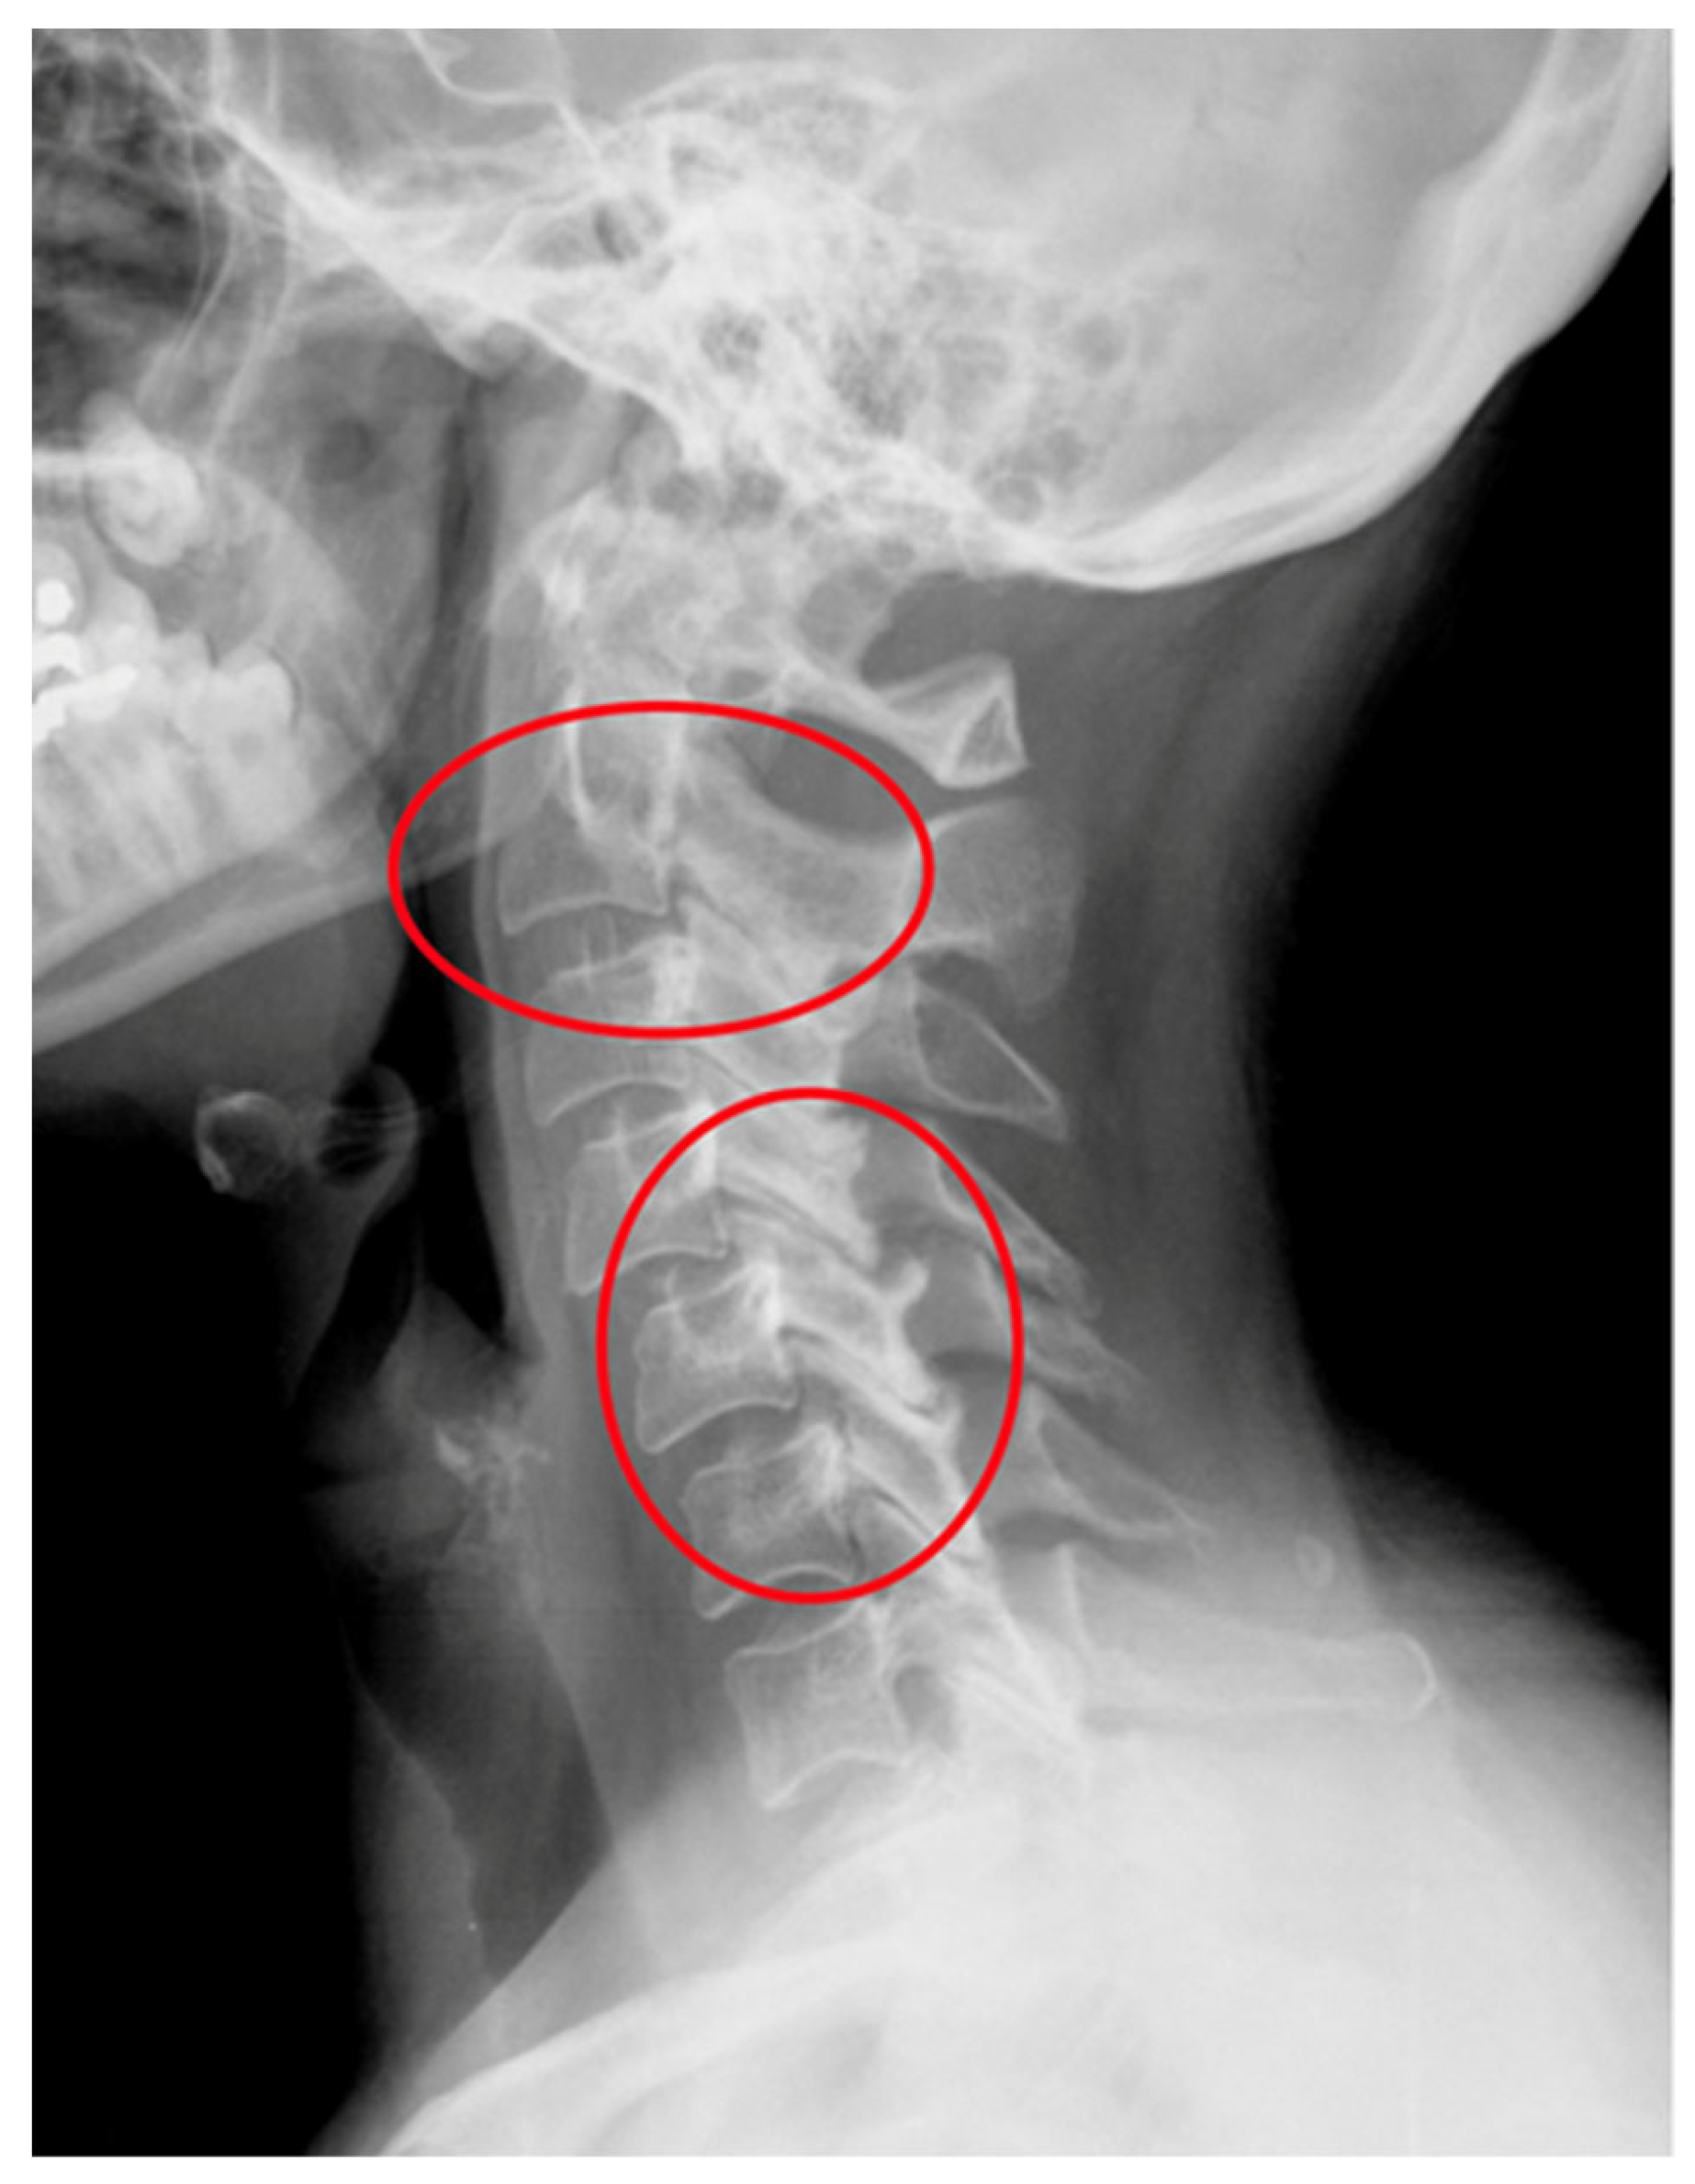

Figure 2.

An X-ray of the cervical spine (lateral view) of a 55-year-old female patient with RA and SAS instability.